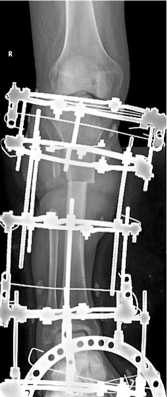

Пациент 44 лет (группа 2) получил ранение при участии в боевых действиях. Диагноз: Сочетанное взрывное поражение таза, обеих нижних конечностей. Множественные осколочные раны промежности, нижних конечностей. Обширная рваная рана правой голени, оскольчатый перелом обеих костей в верхней и средней трети с первичным дефектом костной и мягких тканей (рис. 7). Обширная рваная рана левой стопы с переломом 1 и 2 плюсневых костей. Острая массивная кровопотеря. Травматический шок 2 степени. Острое повреждение почек.

После стабилизации состояния и восстановления функции почек через 34 дня после ранения выполнили повторную хирургическую обработку раны, некрэктомию большеберцовой и малоберцовой костей, ОУ правой голени, ВЧКДО по Илизарову. Дефект большеберцовой кости составил 11 см (рис. 8).

Через 126 дней после ранения (на 92-е сутки после ОУ) выявили признаки сращения отломков и выполнили остеотомию в нижней трети большеберцовой кости (рис. 9 и 10, а).

Удлинение проводили в течение 137 дней после укорочения (рис. 10, б) до 263-го дня после ранения (рис. 10, в). Сращение в зоне контакта отломков отметили на 192-й день после ОУ. В последующем проводили «воспитание регенерата» методом «аккордеона». Созревание регенерата отметили через 108 дней после прекращения удлинения. На 371-й день после ранения выполнили демонтаж АВФ. Продолжили реабилитацию в течение 60 суток (рис. 11).

Рис. 7. Фото и рентгенограмма правой голени при поступлении

Рис. 8. Рентгенограмма правой голени после острого укорочения

Рис. 9. Фото правой голени перед остеотомией

Рис. 11. Телерентгенограмма и фото нижних конечностей пациента после окончания лечения

Рис. 10. Рентгенограммы: а — правой голени после остеотомии; б — правой голени в процессе удлинения большеберцовой кости; в — обеих голеней после окончания удлинения правой большеберцовой кости

Общий срок лечения составил 431 день, ИВФ — 29,7 сут./см. Остаточное укорочение 2 см. Анатомический результат по шкале ASAMI — хороший, функциональный — хороший.